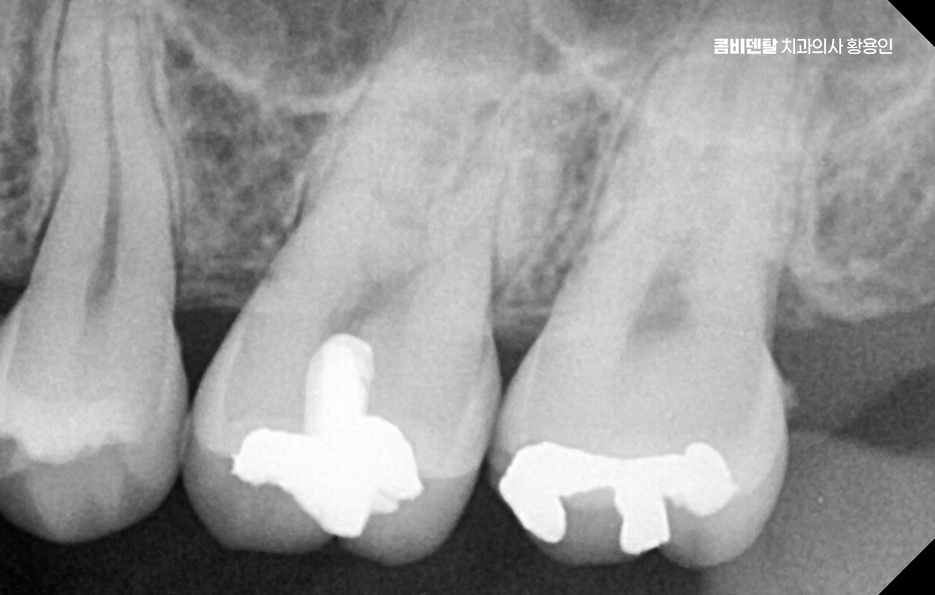

인레이 치료 후 통증으로 먼저 가장 흔한 원인 중 하나는 ‘2차 충치’, 즉 인레이 아래에서 새롭게 생긴 충치로 인레이는 정밀하게 본을 떠서 제작되는 맞춤 보철물이지만, 시간이 지나면서 접착제로 붙인 부분이 조금씩 마모되거나 틈이 생길 수 있어요.

이런 틈 사이로 음식물 찌꺼기나 세균이 침투하게 되면 겉으로는 멀쩡해 보여도 안쪽에서부터 충치가 서서히 진행될 수 있는 거예요. 특히 인레이 치료 후 시간이 오래 지났다면, 그 접착제가 녹아서 접합력이 약해졌을 가능성도 있고, 또한 평소 구강 위생 상태가 좋지 않았다면 세균의 공격을 더 많이 받았을 수 있는 거예요.

이런 2차 충치는 인레이로 가려져 있어서 겉으로 보이지 않는 경우가 많고, 증상이 꽤 진행된 이후에야 시림이나 씹을 때의 통증, 잇몸 부위의 묵직한 불편감으로 드러나는 경우가 대부분이다 보니 사실상 증상으로 문제를 인지하는 경우에는 2차 충치가 상당 수준 진행된 경우도 많이 있어요

인레이 치료 후 통증 두 번째 원인으로는 인레이와 주변 치아 사이의 틈이 발생한 경우로 처음 치료할 당시에는 인레이가 정확히 맞았더라도 시간이 지나면서 치아는 미세하게 마모되거나 잇몸이 내려가고, 인레이의 치아 사이 경계 부위가 어긋나면서 틈이 생긴 경우로 쉽게 말해 인접면 충치가 발생한 경우도 있는데 이 틈은 충치뿐 아니라 치주염이나 이물감, 시림으로도 이어질 수 있으며 잇몸 자극이 생기기도 하고, 인접 치아 사이에서 음식물이 자주 끼게 되는 문제도 발생할 수 있어요